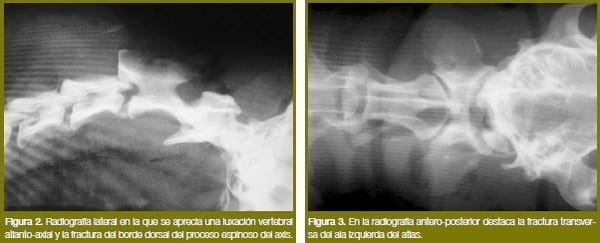

Se toman imágenes radiográficas laterales y antero-posteriores de la región cervical. En la radiografía lateral (figura 2) se distingue claramente la presencia de una luxación vertebral atlanto-axial, con un descabalgamiento dorsal del axis con respecto al atlas, y fractura del borde dorsal del proceso espinoso de la 2ª vértebra cervical (axis). En la vista antero-posterior (figura 3) destaca la fractura transversa del ala izquierda del atlas. En ambas posiciones radiográficas existe un importante enfisema gaseoso que ocupa tanto espacio a nivel subcutáneo como en las zonas intermusculares, consecuencia de los importantes desgarros que han provocado las mordeduras en estos tejidos.